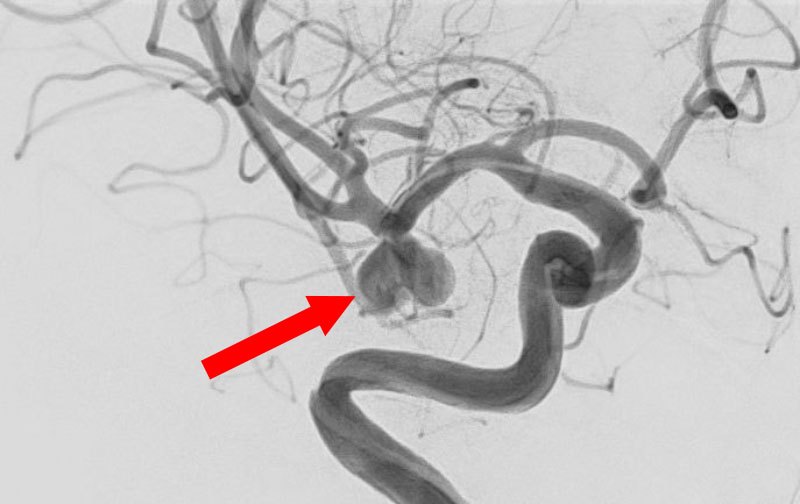

No.1600 手術後